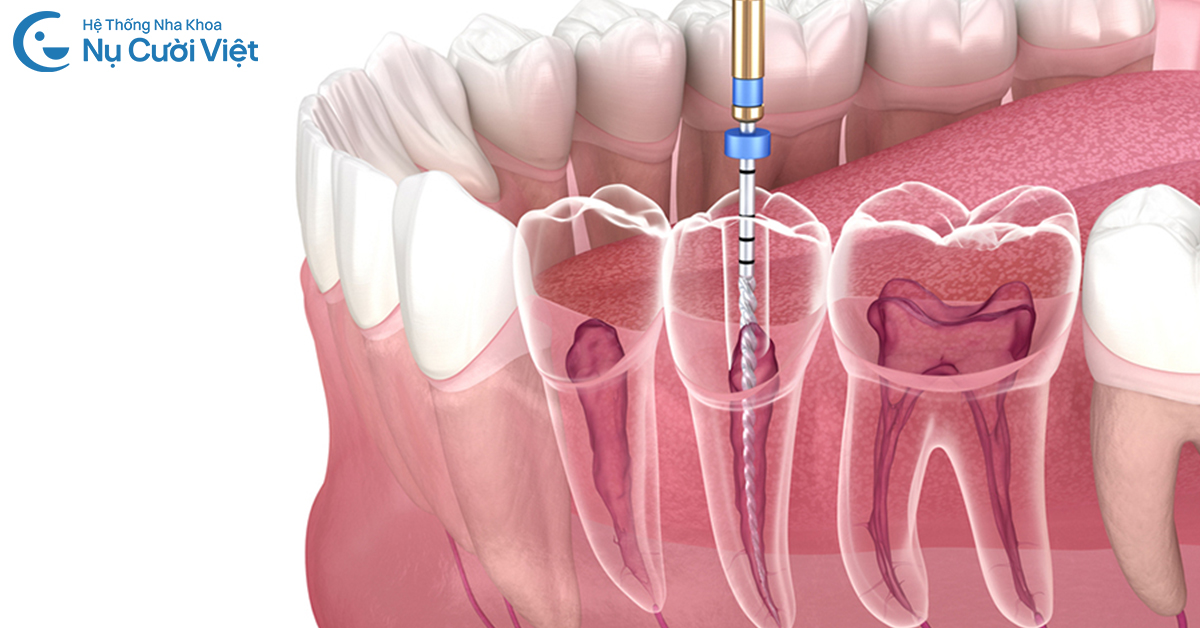

Do đó, điều trị tuỷ KHÔNG sử dụng thuốc diệt tuỷ chứa thạch tín hay bất kỳ hoá chất độc hại nào. Việc lấy tuỷ răng, làm sạch ống tuỷ đều được thực hiện bằng máy nội nha hiện đại, kết hợp gây tê phù hợp để đảm bảo sự an toàn, không đau và thoải mái nhất cho khách hàng.

• Trường hợp tuỷ viêm nặng hoặc chết tuỷ toàn bộ: Bác sĩ tiến hành gây tê, lấy tuỷ trực tiếp, làm sạch hoàn toàn mô tuỷ viêm hoặc hoại tử bằng máy nội nha hiện đại, sau đó trám bít ống tuỷ và trám lại răng theo đúng chuẩn y khoa, giúp giữ lại răng duy trì chức năng ăn nhai lâu dài. Toàn bộ quá trình lấy tủy, làm sạch và tạo hình ống tủy tại Nụ Cười Việt được thực hiện 100% bằng máy điều trị nội nha, cho phép kiểm soát chính xác chiều dài ống tủy, mức độ làm sạch và hạn chế tối đa tổn thương mô răng xung quanh.

Việc sử dụng máy điều trị nội nha trong toàn bộ quy trình không chỉ giúp nâng cao độ chính xác, mà còn góp phần rút ngắn thời gian điều trị và giảm cảm giác khó chịu cho khách hàng. Quan trọng hơn, phương pháp này cho phép bác sĩ kiểm soát ca điều trị một cách chủ động, thay vì phụ thuộc vào các biện pháp hóa học mang tính thụ động và tiềm ẩn rủi ro.